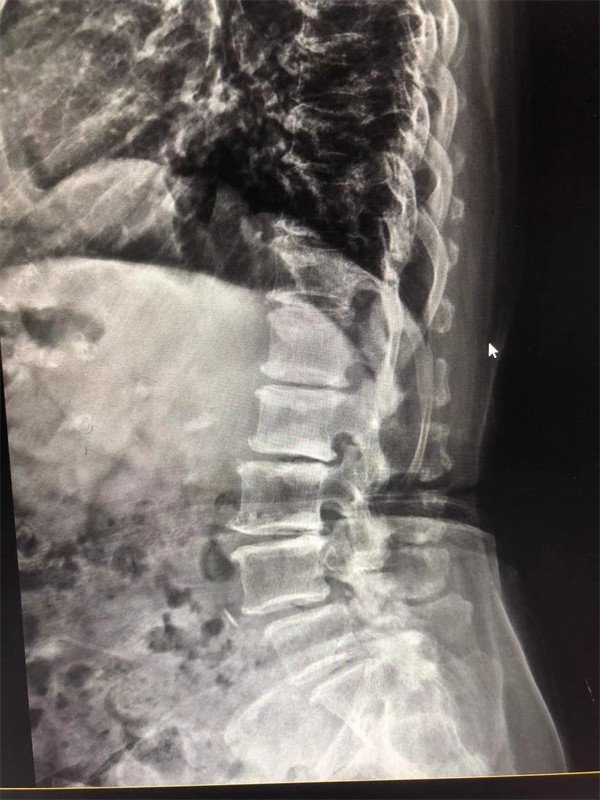

戈主任仔細詢問阿婆病情癥狀,綜合查體及MRI片情況,認為阿婆有明顯的腰椎滑脫,腰椎管狹窄,這是引發(fā)阿婆病痛的主要因素。

手術前↓